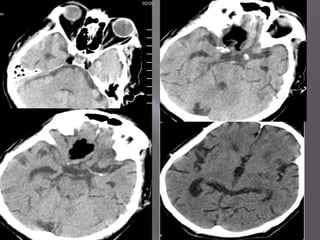

WHAT ARE THE POSSIBLE CAUSES OF THIS

ABNORMALITY?

Causes ;

1).AR I AL I N C

TER          FAR TS.

O usi on of per f or at i ng

ccl

ar t er i es f r om t he t i p of t he

basi l ar ar t er y.

2). VEN U I N C

O S FAR TS. Thr om i c occl usi on of

bot

t he vei n of G en and/or st r ai ght si nus.

al

3).SEVER AN XI A.

E O